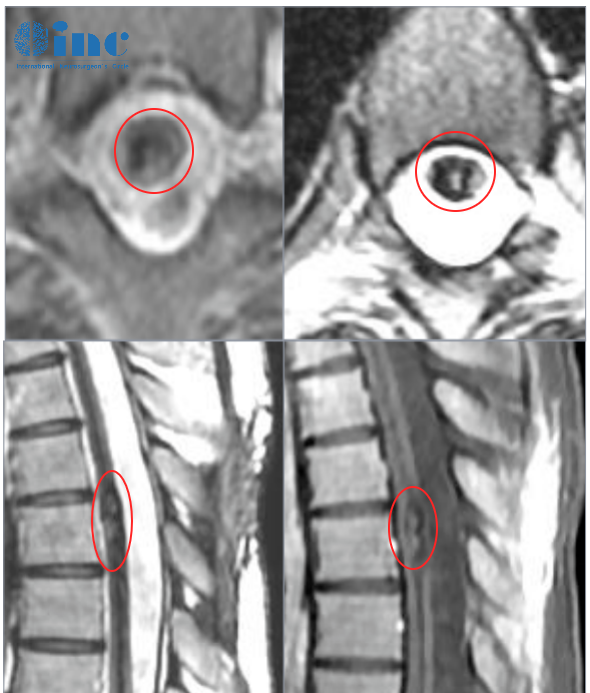

诊断:胸髓(T6)内占位:海绵状血管瘤;椎管扩大减压术后

2、海绵状血管瘤偏腹侧,位置较深,脊髓表面病灶显现不明显,术中超声辅助定位

2、髓内半椎板切除术的发明

半椎板切除术主要根据髓内海绵状血管瘤的定位选择患者位置,患者在俯卧位进行手术。医生在病变区域通过标准方法,即通过背根入口区或中线脊髓切开术接近深部病变。除了精确的定位和脊髓的较佳进入区域,解剖技术可能会影响髓内海绵状血管瘤的手术结果。手术过程中,使用双较钳和微型剪刀来断开引流血管是的重要。在确定手术平面后,应以锋利的解剖方式进行病灶切除,以避免损伤正常脊髓组织。

(A-C)3D-CT扫描显示位于C1-2水平的髓内CM的术后图像。(B)在术中脊髓表面观察到含铁血黄素染色。(C)完全切除髓内CM,显示髓鞘切开的程度。